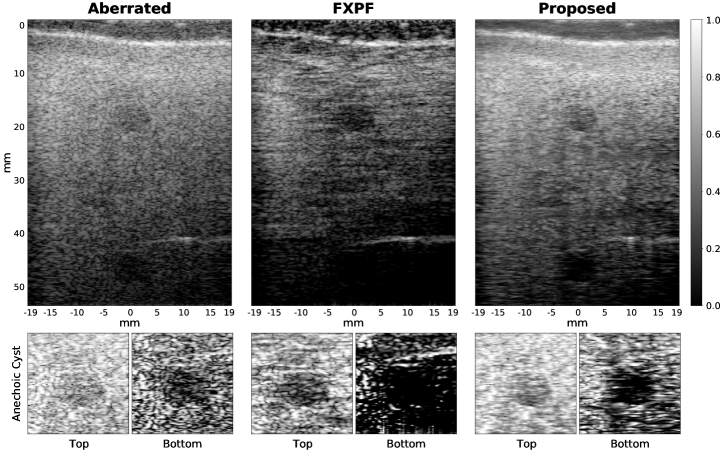

Figure 4: Comparison of methods for the experimental phantom aberrated with a physical aberrator layer. Images in the first row are shown on a 60 dB dynamic range.

Fig. 4 presents the results for the experimental phantom aberrated with a physical aberrator. To enhance visual comparability, the top and bottom cysts were cropped and displayed under their corresponding images, where each horizontal line of the cropped images was normalized to its maximum intensity. While the FXPF method provided a higher contrast for the top cyst, it resulted in an overestimation of its size. In contrast, the proposed method recovered the true cyst borders more accurately, particularly for the bottom cyst.